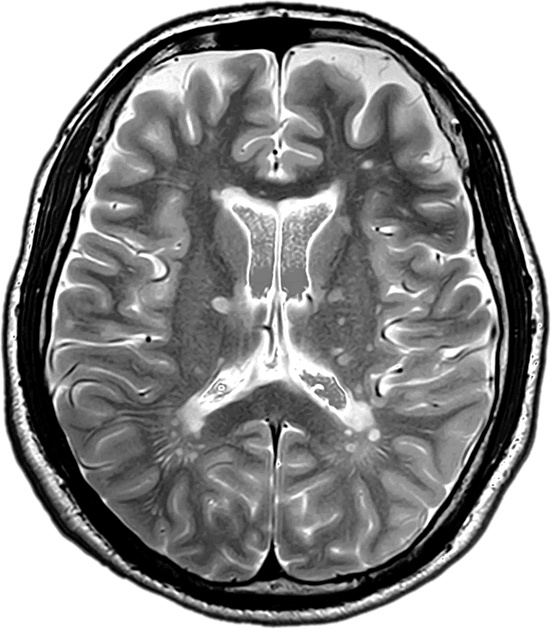

Иллюстрация к книге — Забывчивость - мое второе ... что-то там. Как вернуть то, что постоянно вылетает из головы [i_004.jpg]

МРТ-снимок мужчины 30 с лишним лет, у которого из-за переутомления случались потери сознания.